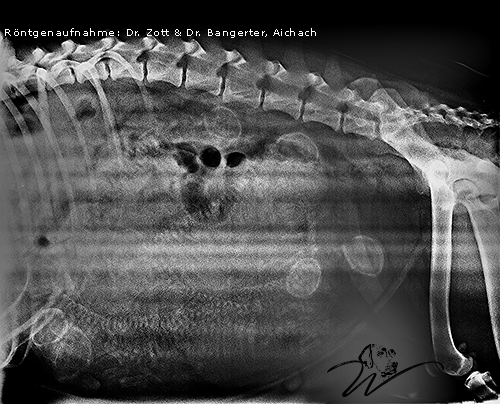

Röntgen am 03. Juni 2019

Heute waren wir zum Standard-Check und Röntgen beim Tierarzt. Neben einem Wirrwarr an kleinen Wirbelsäulen sind sechs Köpfchen mit Sicherheit auszumachen. Aber es können auch Welpen hintereinander liegen und dadurch nicht erkennbar sein. (Die Gebärmutter beim Hund ist in zwei „Gebärmutter-Höcker“ geteilt, jeweils einer auf der rechten und linken Körperseite.) Das heißt wir müssen uns überraschen lassen wie viele Babys es werden. Leila bekommt weiterhin calziumreiches Fleisch, Fisch, Gemüse und wertvolle natürliche Zutaten wie kaltgepresste Öle, etc. Alles frisch jeden Tag zubereitet.

Übrigens ist die Strahlendosis derart gering, dass es keine Schäden an Welpen oder Mutter gibt. Jeder Züchter lässt seine Hündin vor dem Geburtstermin röntgen, um in etwa eine Ahnung zu bekommen wie groß der Wurf sein wird.

Leila bringt heute 37 kg auf die Waage, ihr Normalgewicht sind 28 kg. Sie trägt also ca. ein Drittel ihren Gewichtes zusätzlich mit sich herum. Das wären bei einem Erwachsenen von 90 kg stolze 30 kg! Also drei große volle Wassereimer! Und trotzdem will das Mädchen spazieren gehen. Nur, sie kann einfach nicht mehr so lange wie sie gerne möchte. Die Hitze momentan macht ihr zusätzlich zu schaffen.